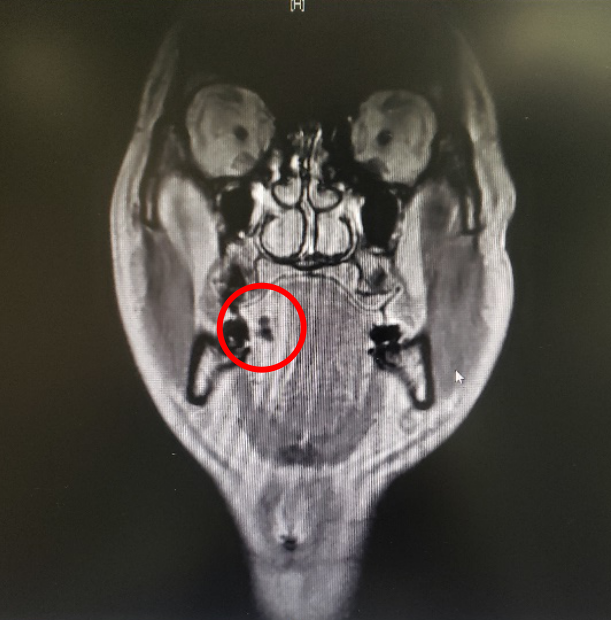

图三:病人的术前MRI

图四:病人的术前MRI

那么这个异物包裹性脓肿里面到底是什么呢?我猜测要不是鸡骨,要不就是鱼刺,但鸡骨的话体积比较大,在CT上一般能看得出来,而且这么大的鸡骨插进舌头,病人的症状会非常明显,不会等到几个月后才来就诊。而鱼骨一般是很纤细的,在CT上是看不出来的,不过我们仔细看影像的话,还是可以在切面上发现小的阻射影的。